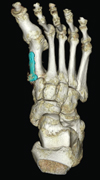

Three-dimensional computed tomography (3DCT) revealed the hallux varus deformity and dorsal dislocation of the second toe (Figure 2(a)). Osteophyte formation was observed at the proximal end of the phalanx. On the coronal image, the surface area of the medial side of the articular surface at the first metatarsal head was decreased by the resection of the bony prominence (Figure 2(b)). Because her symptoms such as pain and gait disturbance had worsened, surgery was performed.

(a)

(b)

(c)